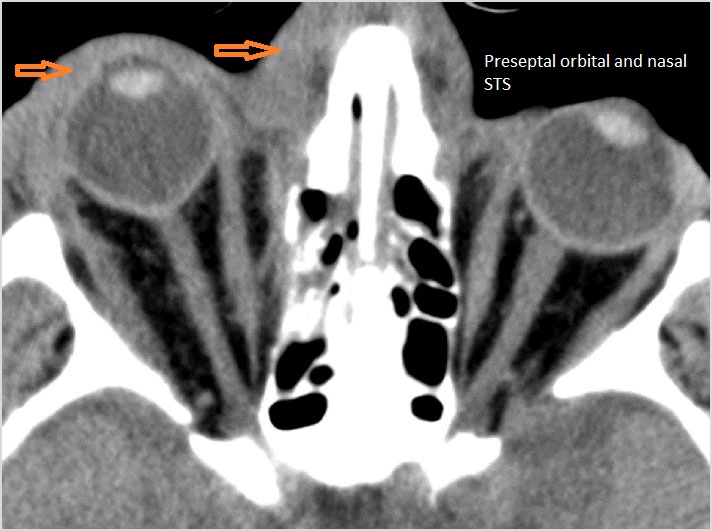

Facial and Scalp Soft Tissues and Airway

There is localized edema, hematoma or abscess within in the facial or scalp soft tissues, SMAS, infratemporal fossa, masticator space or oral cavity. [Yes/No]

The preseptal soft tissues including the lacrimal gland and sac are normal. [Yes/No]

The circumferential extraconal and the intraconal orbital fat are infiltrated. [Yes/No]